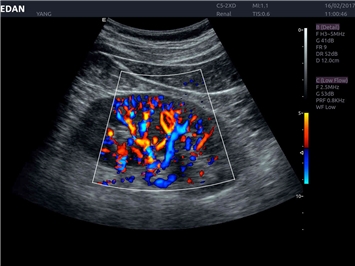

• Исследования малых органов

Недопплеровская визуализация кровотока:

Да